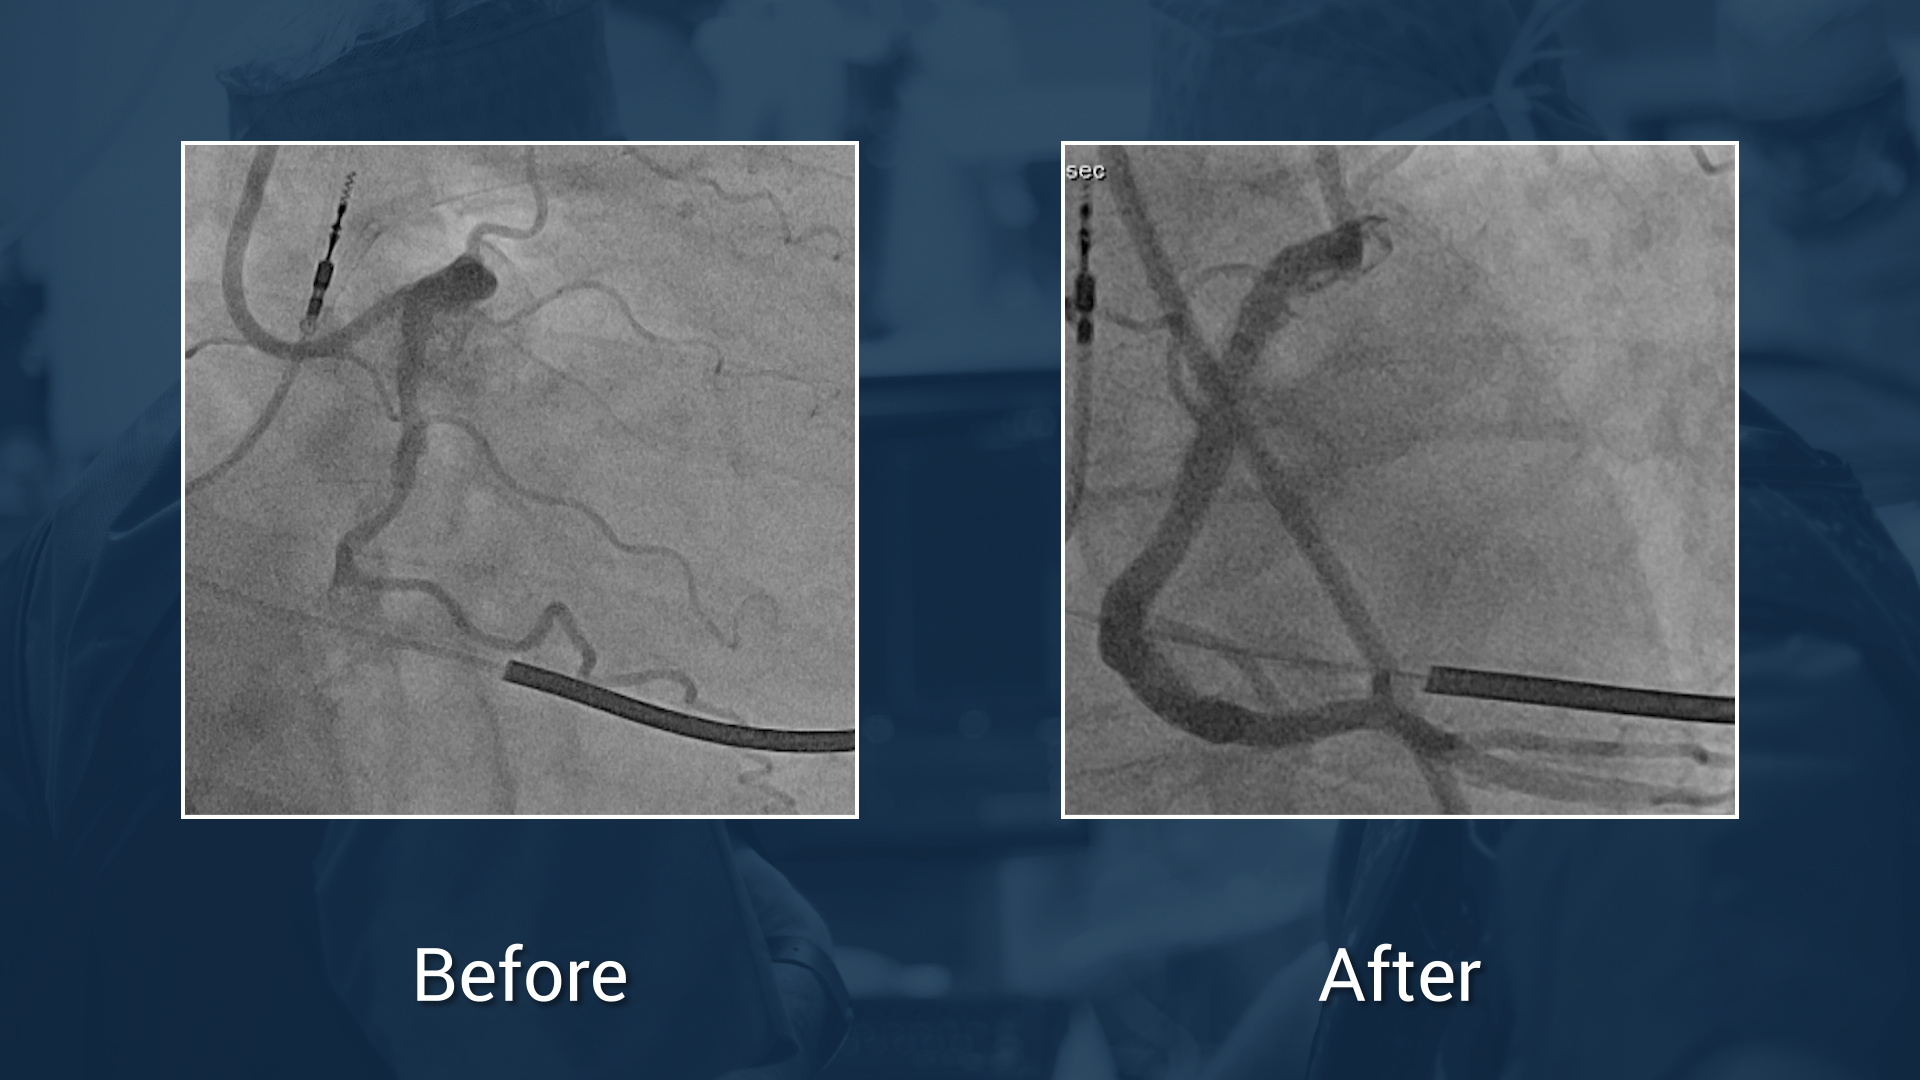

Protocole:

• OptiRAY® (ioversol)

• Concentration: 350 mgl/mL

• Volume: 170 ml

Total Time: 77 min

Exposure Time: 36 min

Exposure: 1704 mGy

Workshop on Complex PCI (UHZ - Bad Krozingen)

We are pleased to announce you that the Guerbet Masterclass which took place on October 2018 at the UHZ (Bad Krozingen, Germany) is available online for all participants and incathlab members. ...